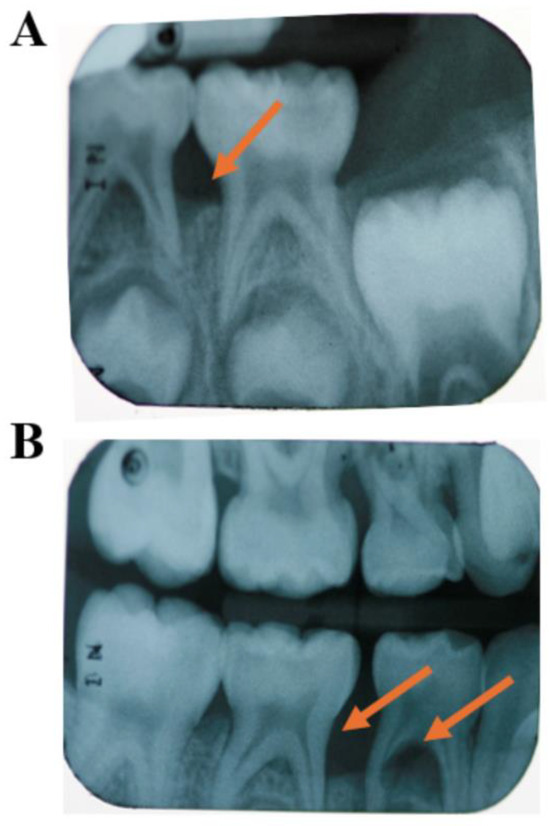

Figure 1.

Clinical Case: 8-year-old African American female diagnosed with C-MIP in primary dentition. Patient smiles with low gingival margin inflammation; however, probing depth > 5 mm in the first molar. In the X-ray, severe bone loss in the lower first primary molars (orange arrow and circle) along with internal and external resorption of the lower left primary first molar in the primary dentition (orange arrow) (A). Permanent dentition in healthy conditions following therapy (SRP+ABX) in the primary dentition (B). (Source of the image [10]).